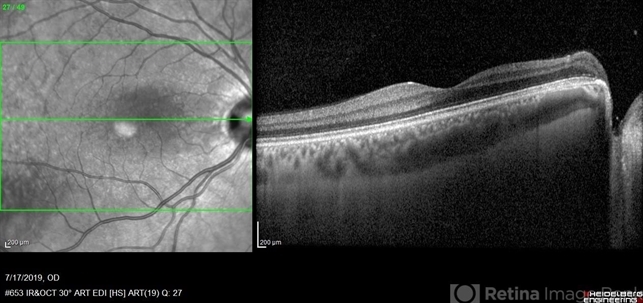

- optical coherence tomography (OCT), optic pit

- Imaging device

- Heidelberg Spectralis 2

- Fundus photograph of 38-year-old healthy man with right optic disc pit, who recently noticed slightly blurred vision in right eye while closing the left eye. BCVA was 20/25 in OD and 20/20 in OS. IOP was 15mmHg OD and 14 mmHg OS. Right fundus exam showed small optic disc pit near the temporal rim of optic disc with abnormal reflex of nasal macula. Left fundus was normal. Late FA of right optic disc showed no leakage or staining of optic disc. Macular OCT showed normal foveal contour with no subretinal fluid or macular edema. There was significant reduction in RNFL thickness in the temporal sector in right eye. Coloboma is clearly seen on vertical OCT scan as well as horizontal scans through right optic pit.